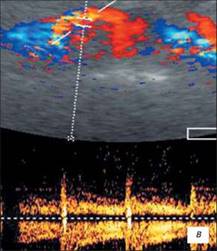

Доплерограма

На малюнку помітно зниження функції нирок виявляється ненасичений інтраренального малюнка, зниження по часу або мінімальної швидкості кровотоку. Всі ці критерії характеризуються патологією і потребують оперативного втручання.

Сканування лівого сечівника через сечовий міхур. На доплерограмах чітко видно криву ретроградногопотіку сечі. Швидкість потіку 0,52m/s, Час 1,16s)

Сканування лівого сечівника через сечовий міхур. На доплерограмах чітко видно криву ретроградногопотіку сечі. Швидкість потіку 0,22m/s, Час 2,38s)

На доплерограмі сечоводів СМР 2,3 і4 ступені спостерігається: делятація сечівника в нижніх і верхніх відділах при середньому або максимальному наповнені сечового міхура, циклічні зиіни діаметра сечівника в нижніх і верхніх відділах: доплерографічна регістрація зворотнього току сечі в сечоводі:стабільне розширення миски: зменшення розмірів нирки.